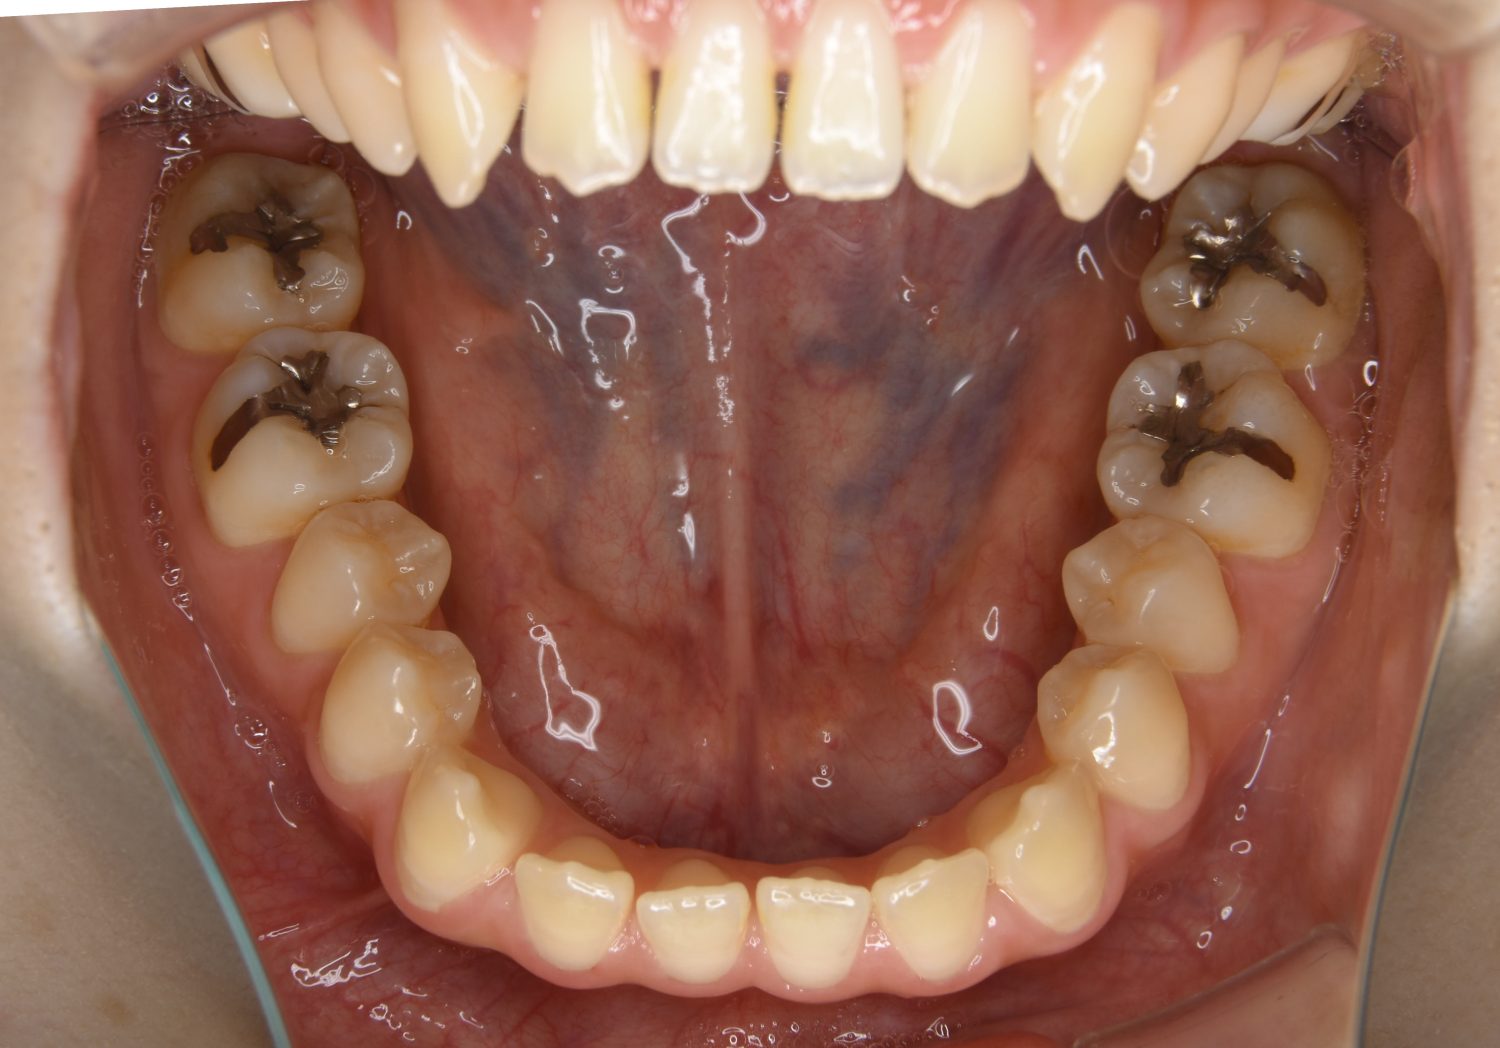

前歯部開咬の症例紹介②

Before

主訴

前歯で物が噛めない

治療内容

上下ラビアルブラケット(唇側装置)に矯正用アンカースクリューを併用し非抜歯で治療を行いました。

上下の前歯が開いており前歯では全く噛めていない状態でした。臼歯の圧下を行うことで機能面のみでなく審美面も改善しました。